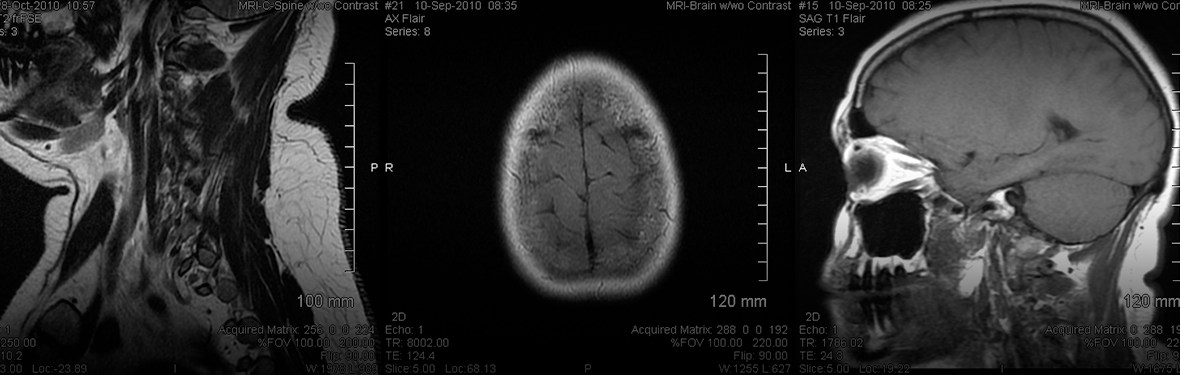

It was like this dark gray gauze was being pulled down over just my left eye. That’s optic neuritis. It lasted about a month, during which time I went to my optometrist, who referred me to an ophthalmologist, who did a ton of tests. The MRI I had then was inconclusive … in other words, no lesions were seen that could have signaled MS at the time.

Fact: There is no clear-cut diagnosis for MS, but rather a battery of tests to rule out other diseases first. Two rounds of MRIs spaced a few months apart is the most definitive way to know.

- MRI of brain and spinal column (with contrast dye)

- Evidence of damage in at least two separate areas of the central nervous system that have happened at two different points in time – this evidence is usually seen in a contrast-dye MRI in the form of lesions, which is where the scar tissue that gives multiple sclerosis its name is seen

Also, fun fact: Get used to the MRIs. Most people with MS get one annually to check on lesion activity. You’re hoping that those white dots are smaller and fewer in number.